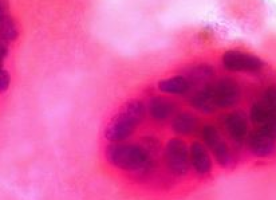

The gene fault, called CHEK2*1100delC, creates a faulty protein that interrupts a cell’s ability to repair damaged DNA, so increasing the number of DNA mistakes that can lead to cancer.